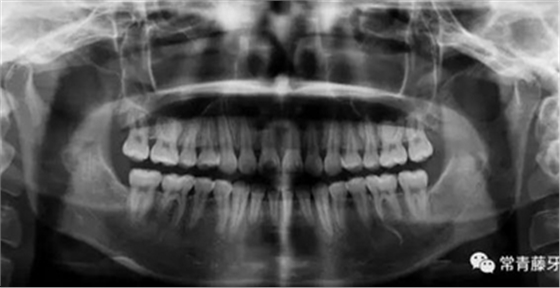

影像學(xué)檢查

曲斷顯示38、48阻生;雙側(cè)TMJ髁突頭略不對(duì)稱。

術(shù)后影像學(xué)檢查

曲斷可見牙根基本平行。